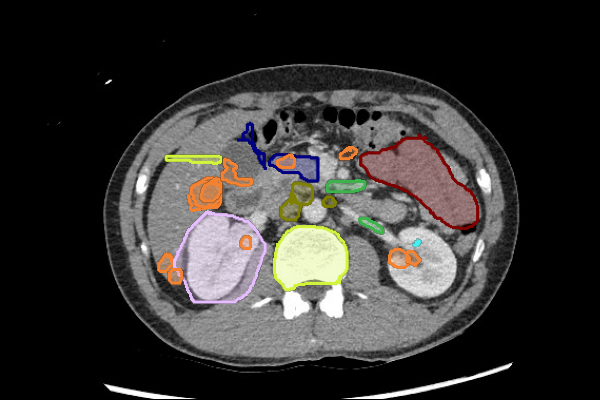

- Liver lesions can be subtle. Use a "Liver" window to increase sensitivity.

- Masses in the mesentery/peritoneum are often overlooked. Take advantage of multiplanar imaging and look in characteristic locations for peritoneal lesions.

- Kidney masses are also overlooked. Look carefully at the collecting system and for renal contour abnormalities.

Mass or Adenopathy

Legend